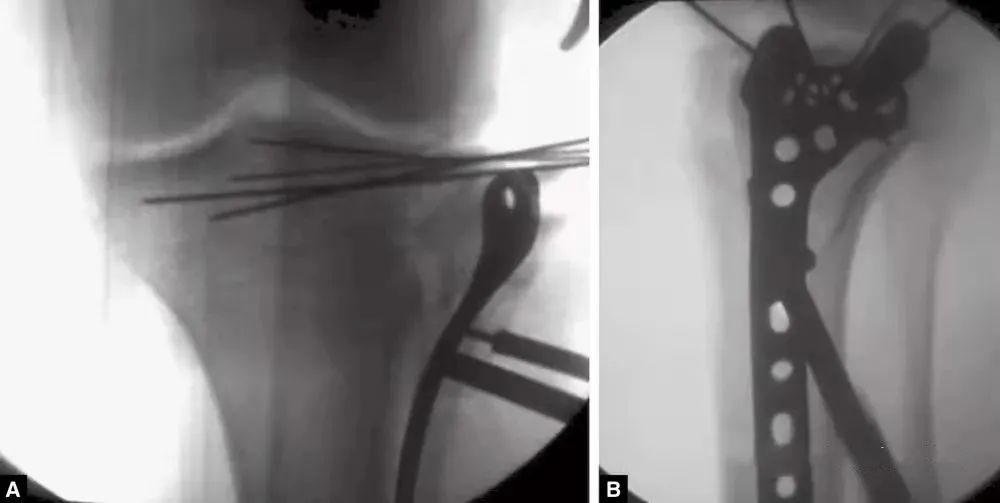

图13 钢板穿过肌肉下平面,远端通过另一个切口贴于骨面

图14 A和B:在最终固定钢板前,在两个方向的透视下检查钢板位置(A)正位片;(B)侧位片

骨折碎块之间的裂缝可以撬开,可能有助于更清楚地呈现关节内骨折并有助于随后的直接复位(图9)。塌陷的关节内的碎片通常有一个完整的强大的软骨下骨支撑,沉积进入薄弱的下面的松质骨。该凹陷的部分必须在钝骨膜剥离子(Freer)的帮助下,将软骨下骨逐渐抬高。这个高度应该从中心开始,并朝向外围(图10)。周围关节区域的边缘嵌入应该被发现和纠正。外周变缘或边缘附着的软组织的高度往往处于正常水平,而且股骨髁也可用来作为复位的参照。一旦出现骨缺损,骨折块需要使用至少两个1mm克氏针临时固定在软骨下骨,穿过骨折区域到达对侧髁(图11)。在骨质疏松的骨或缺损无法修复的区域,软骨下的腔隙用松质骨或人工骨移植(图12)。一旦关节的表面被解剖修复,骨碎块被替换,用1mm软骨下克氏针重建(图13)。最终修复通过透视确认(图14A和B)。选择合适的支撑钢板,能对提高关节面起到很好的支撑作用,尤其是近端的锁定螺钉能起到类似木筏样的支撑效果。